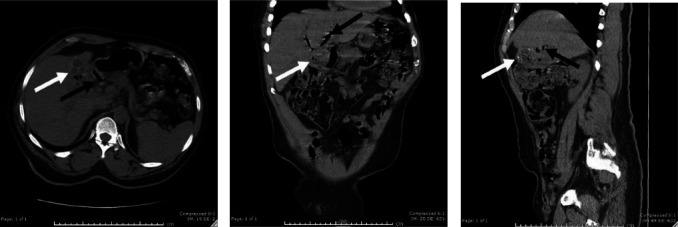

Background: Cholecystoenteric fistulae are rare complications of gallstone disease, with a reported incidence of 0.5% to 0.9% of cholecystectomies. Cholecystoduodenal is the most common fistula followed by cholecystocolonic fistulae. Summary: We report a case of pneumobilia resulting from a combined cholecystoduodenal and cholecystocolonic fistulae treated with a laparoscopic subtotal cholecystectomy and open repair of the enteric fistulae. Conclusion: Combined cholecystoduodenal and cholecystocolonic fistulae are an extremely rare complication of gallstone disease, and meticulous preoperative planning and operative dexterity are needed to safely manage these unusual fistulae.